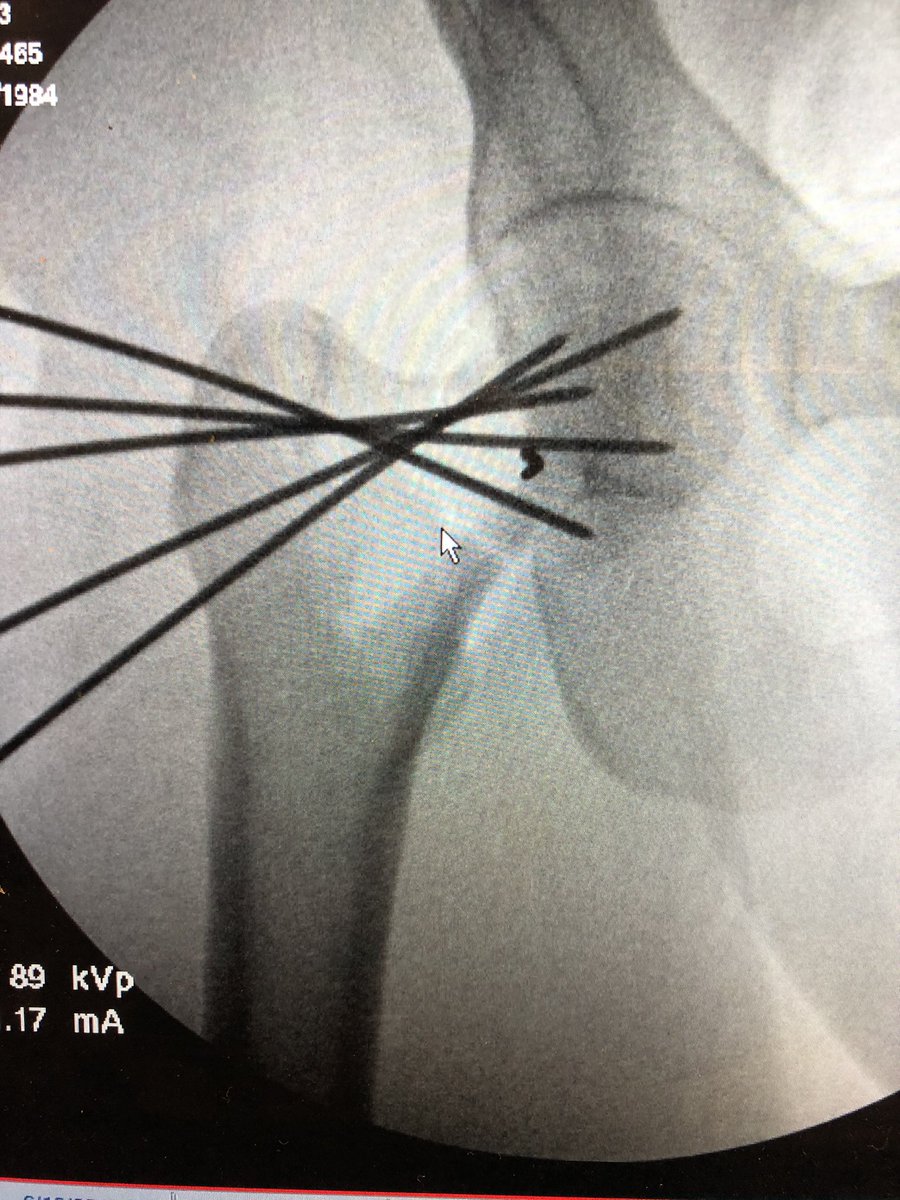

Just a little midnight fun when not on call #orthotrauma #HopkinsOrtho #femoralneckfracture #openreduction #SmithPetersen #lifeinthetimeofcovid19 #fns

@starsmore_j It is DePuy Synthes “FNS-Femoral Neck System”